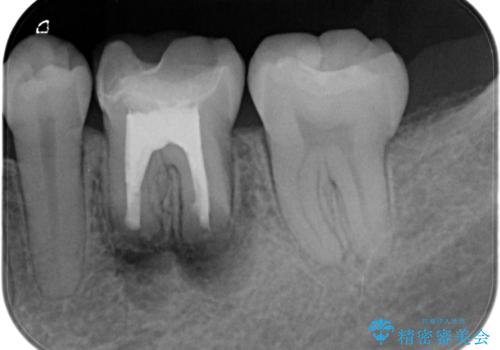

- 昔他院で根管治療を行った歯の病気が再発したことを主訴に来院されました。

レントゲンにて根尖に病変を認め、根尖性歯周炎の診断のもと以下の治療をご提案しました。

外科的歯内療法は根尖性歯周炎の治療における選択肢の一つです。

手術が必要ですが、通常の根管治療では解決できない解剖学的要因も解決できる可能性があります。